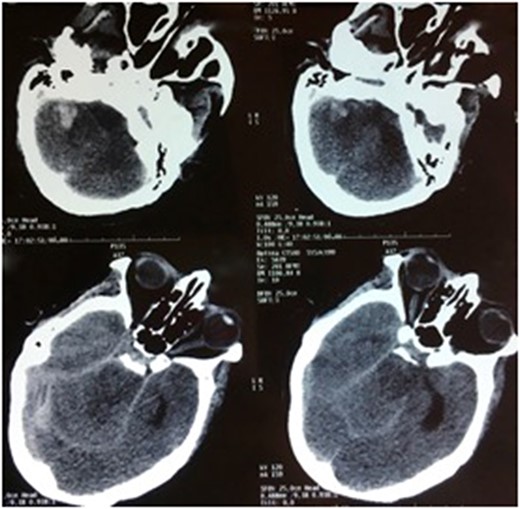

We report a case of a 51-year-old female with no medical history presented for sudden severe headache radiating down her neck associated with nausea, vomiting and photophobia, followed shortly by unconsciousness. On the admission, she scored nine on the Glasgow coma scale with no motor deficit. Cranial computed tomography (CT) performed at admission revealed a sub arachnoid hemorrhage with a nonsurgical right cerebellar hematoma and no intraventricular hemorrhage not indicating an external drainage (Fisher IV) (Fig. 1).

CT scan, axial sections, showing a FISHER IV subarachnoid hemorrhage with a right cerebellum hematoma.